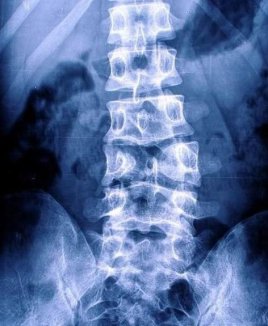

蝴蝶椎是一种脊柱椎体畸形,是椎体的两个软骨中心联合异常,椎体成为

椎体发育异常——蝴蝶椎 蝴蝶椎是一种脊柱椎体畸形,由于椎体的两个

79蝴蝶椎是一种脊椎畸形,是由于椎体两半之间持续存在脊索组织而

02,两边都有一个半椎体,就像脊柱里长了个蝴蝶,称之为"蝶形椎"